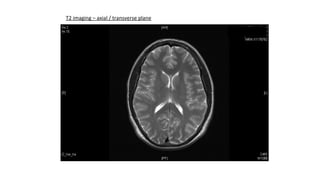

T2 imaging – axial / transverse plane

T2 imaging